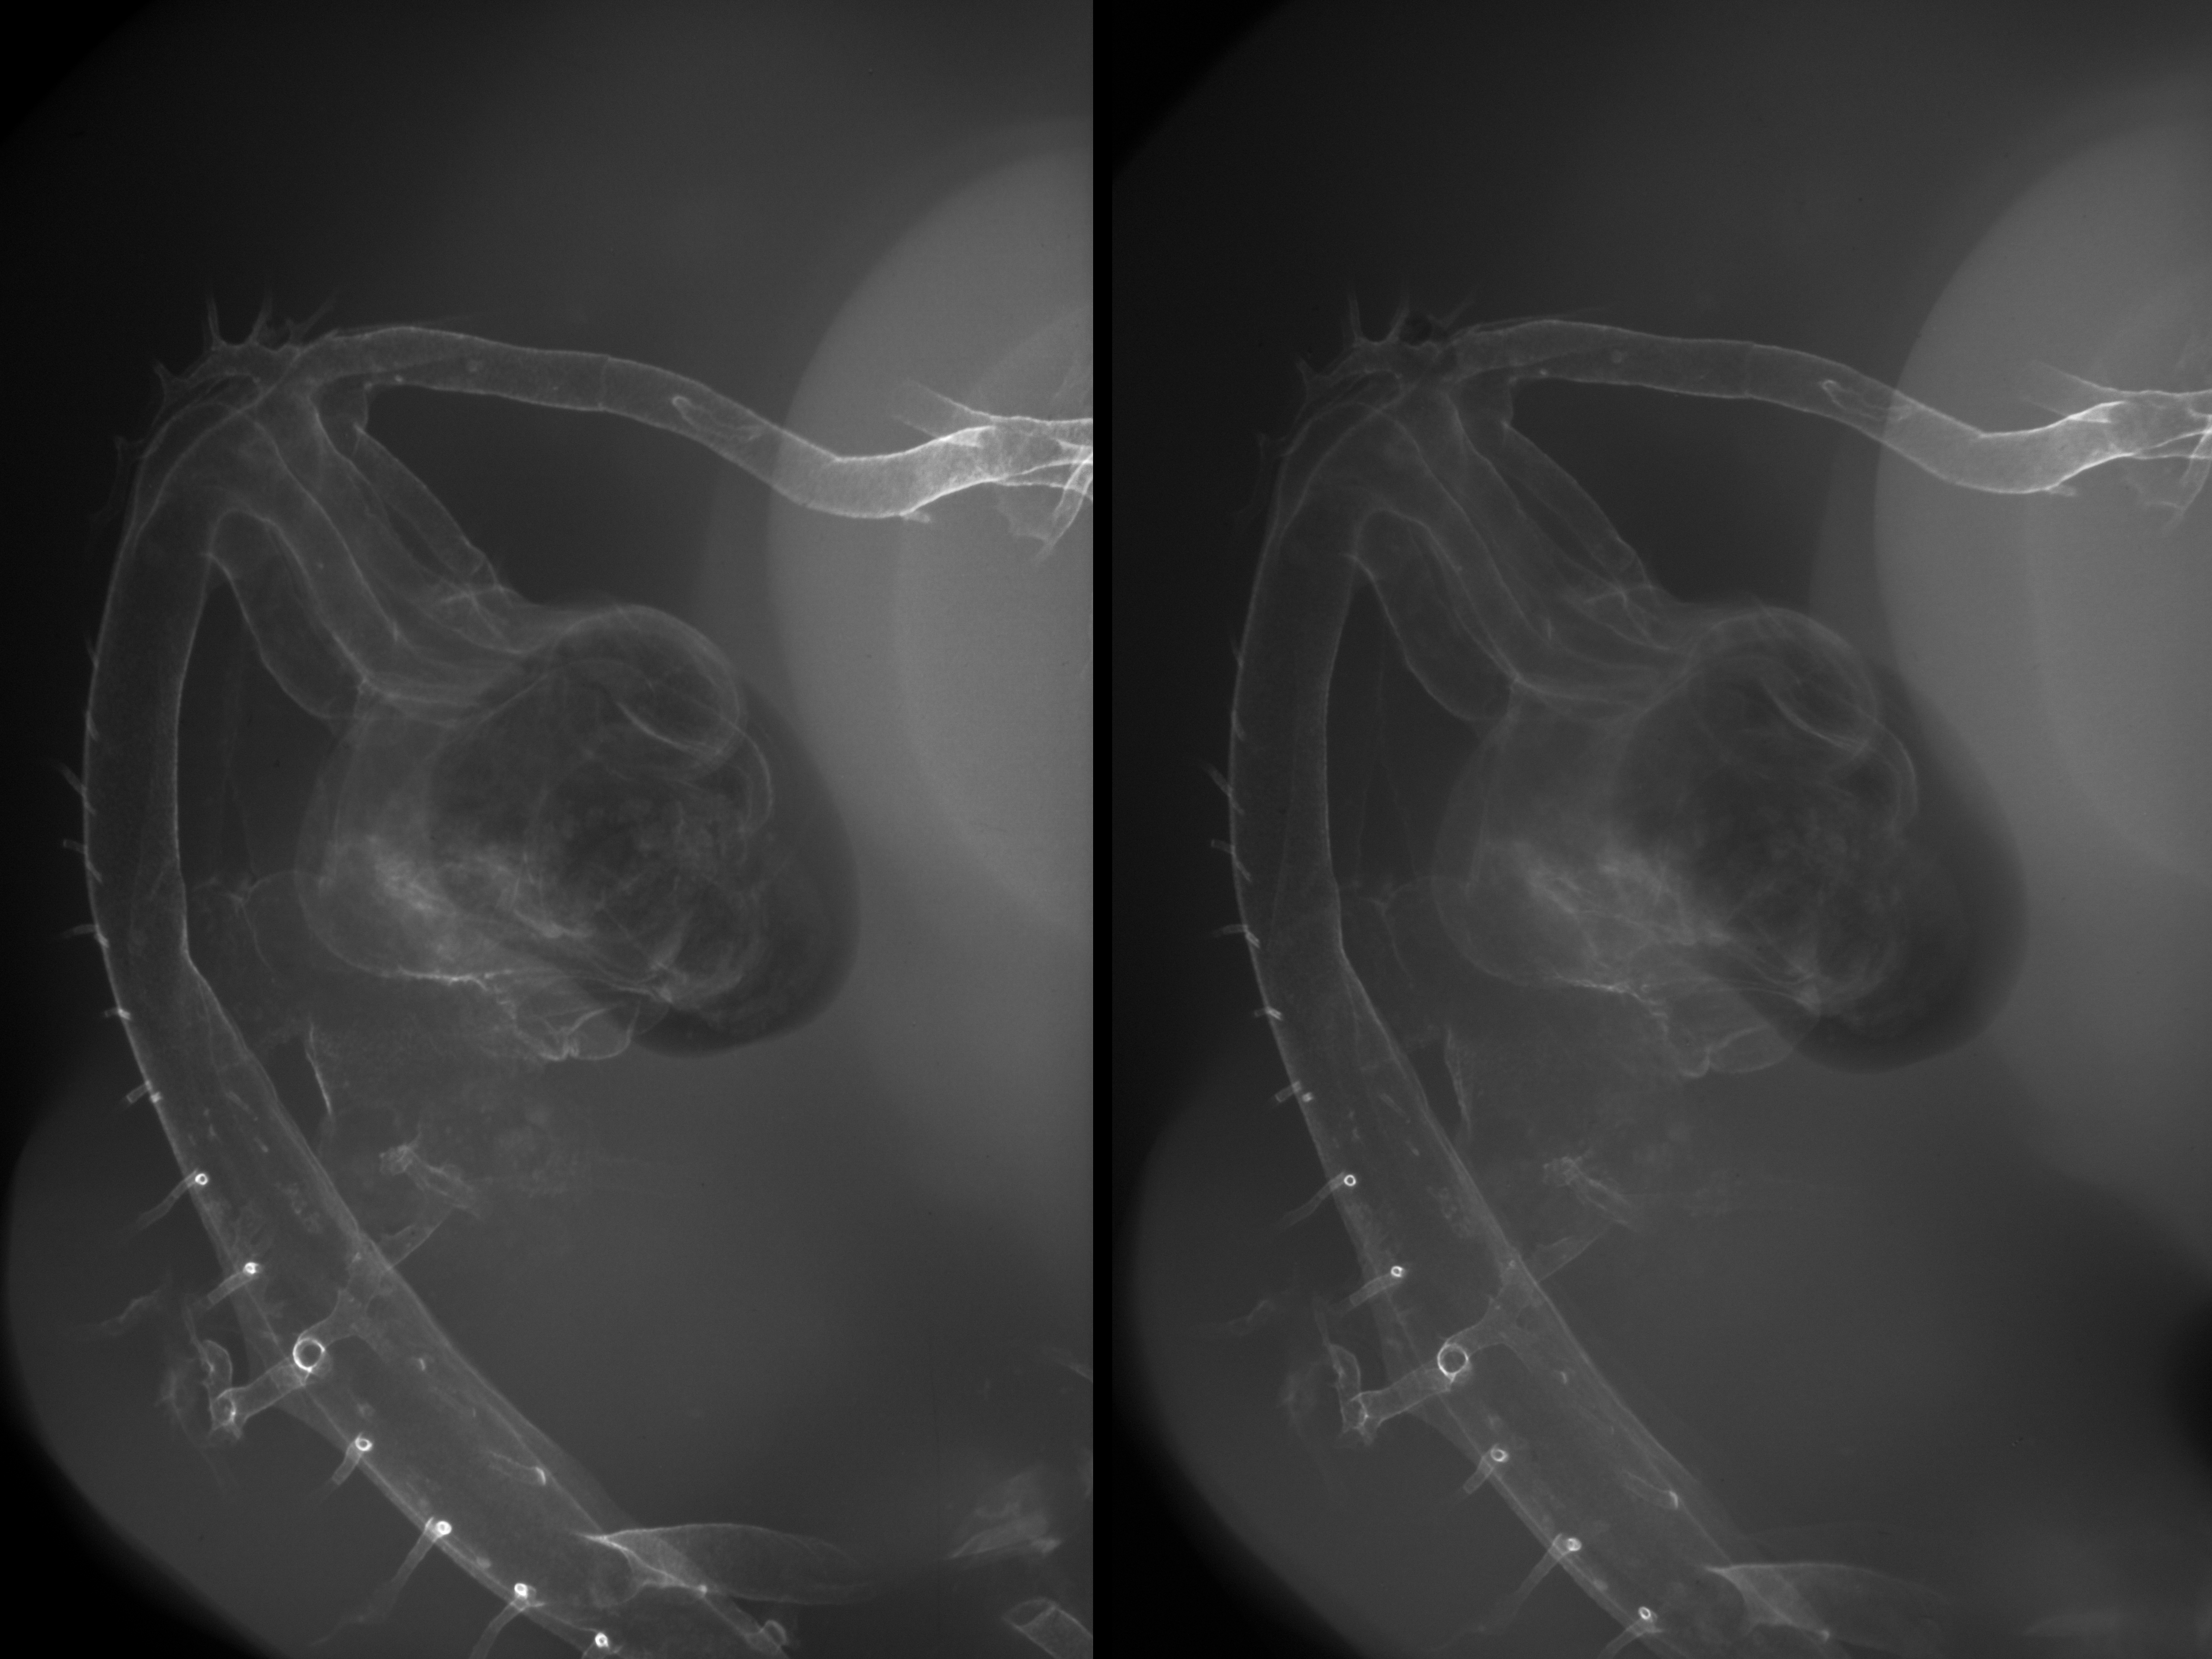

Chick Embryo Microangiography

Hamburger-Hamilton (HH) Stage 27 (approx. 5 - 5.5 days)

Stereo X-Ray Micrographs